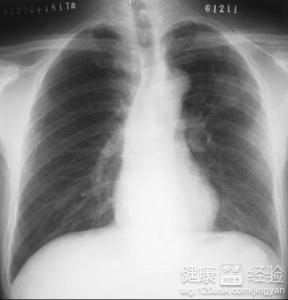

結核不會導致擴張性心肌病,結核桿菌除了感染肺導致肺結核,還可以通過血液傳播到骨和腎引起骨結核和腎結核,泌尿道也了發生結核,肺結核患者如果吞下了痰可能導致腸結核,但是沒有聽說過肺結核會傳播到心髒引起病變的。所以肺結核與擴張性心肌病沒啥關系。如果你以前有肺結核,治愈後會留下鈣化皂,雖然可能會復發,但是復發的概率很小。

1而且擴張性心肌病病因還沒弄明白,其診斷是用排除的方法,就是排除有明確病因導致的擴張性心肌病,如果說結核導致擴張性心肌病,這一點上也是說不通的。擴張性心肌病可能與病毒感染有關系,此外,還與遺傳有關,我發現很多病因不明確的疾病都與遺傳有點關系。

2此外,擴張性心肌病還與免疫有關,尤其是細胞免疫,擴張性心肌病患者體內與細胞免疫有關的某些細胞的數量與正常人相比降低了。這些前面所講的原因都是可能原因,沒有確定的證據證明,真正的原因在未來應該可以探索出來。

3擴張性心肌病的整個發病過程比較緩慢,一般中年人是高發人群,剛開始的時候症狀比較輕微,很容易被忽視,所以無論是哪一類人群,發生異常的現象都應該及時檢查。開始的時候在干重活受累的時候出現呼吸困難,到後面輕微的活動就會導致呼吸困難。

擴張性心肌病沒有確切的病因,一旦發現,應該及時治療,可以延緩病情的進展,不能完全根治,有些嚴重的時候需要心髒移植。由於與遺傳有關,家屬更要注意身體,要注意休息。